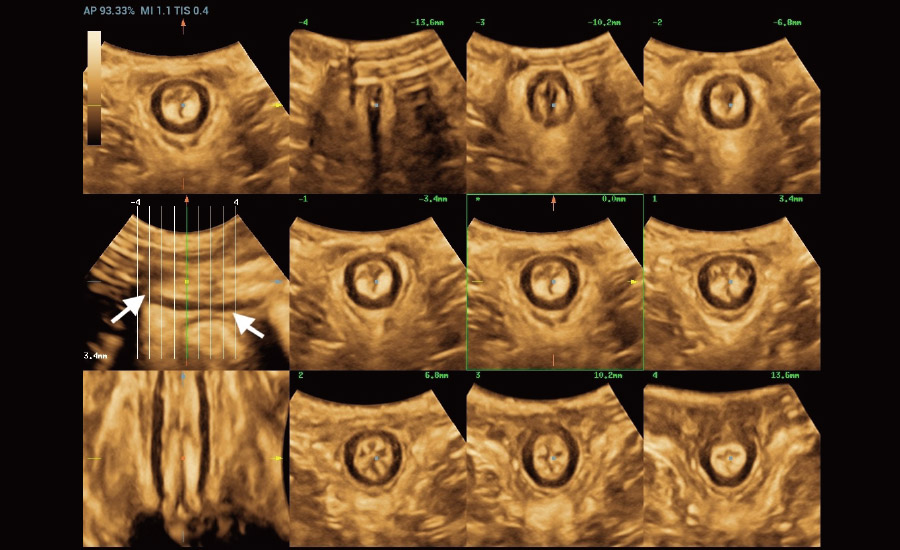

Informa??es abrangentes adaptadas aos cenƔrios

Por meio da combina??o de algoritmos avan?ados e do conhecimento especĆfico da regi?o, a inovadora solu??o Smart Scene permite a identifica??o automĆ”tica das caracterĆsticas do tecido e fornece diagnĆ³stico especĆfico dos Ć³rg?os com informa??es completas. Com base na identifica??o automĆ”tica de cenĆ”rios, a solu??o realiza n?o apenas a varredura 2D inteligente com configura??es e medidas automĆ”ticas, mas tambĆ©m oferece informa??es 3D abrangentes em todas as etapas, desde a otimiza??o de imagens volumĆ©tricas atĆ© a difĆcil obten??o de planos 2D, e a quantifica??o durante todo o procedimento. Ele ajuda a reduzir em grande parte a dependĆŖncia de habilidades clĆnicas, ao mesmo tempo que aumenta a precis?o, a confian?a e a eficiĆŖncia no diagnĆ³stico.

- Protegendo novas vidas com solu??es em fertilidade e obstetrĆcia

Fertilidade

ObstetrĆcia